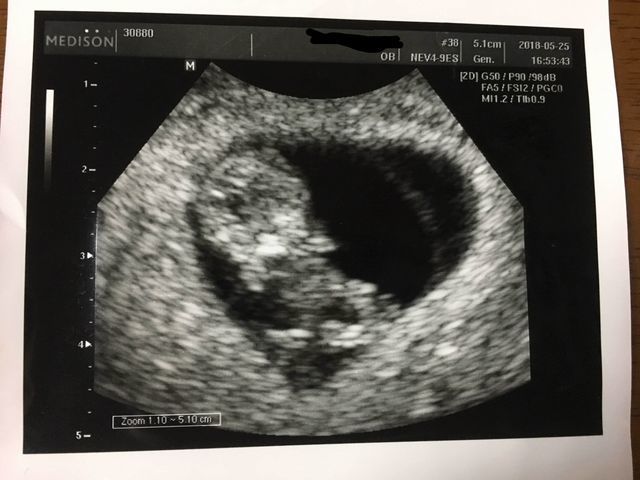

エコー写真撮影時のエピソード(妊娠16週目:16w0d)

まさかの足での敬礼。産婦人科の先生も、足で敬礼してる子はなかなかいないねって笑ってました。もっと前に撮ったエコーではここまで顔立ちハッキリしてなくわからなかったですが、、この時のエコーは鼻と口元が主人にそっくりでびっくり。主人に「似てるね」って話したら、「そうかなぁ?」って照れながら喜んでました。